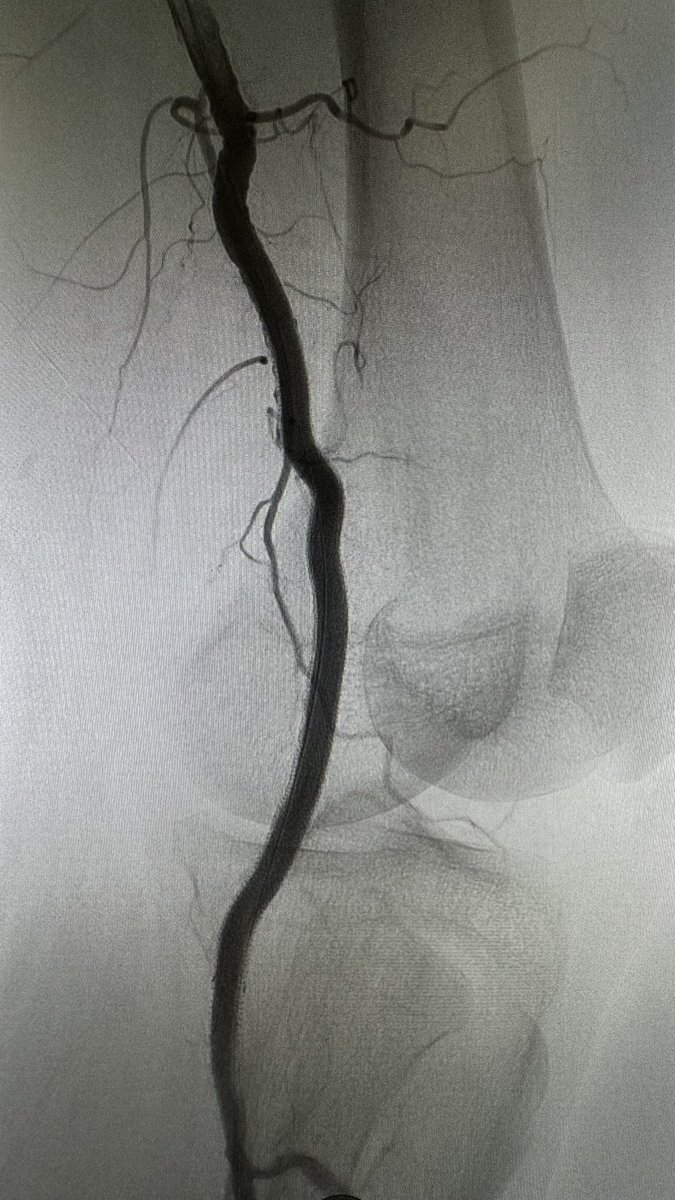

Thank you @cfbechara for the visit to Atlanta and @EmoryVascSurg. Excellent and well-attended talk on decreasing stroke risk in thoracic aortic endovascular interventions at @VascularGeorgia foundation dinner last night.